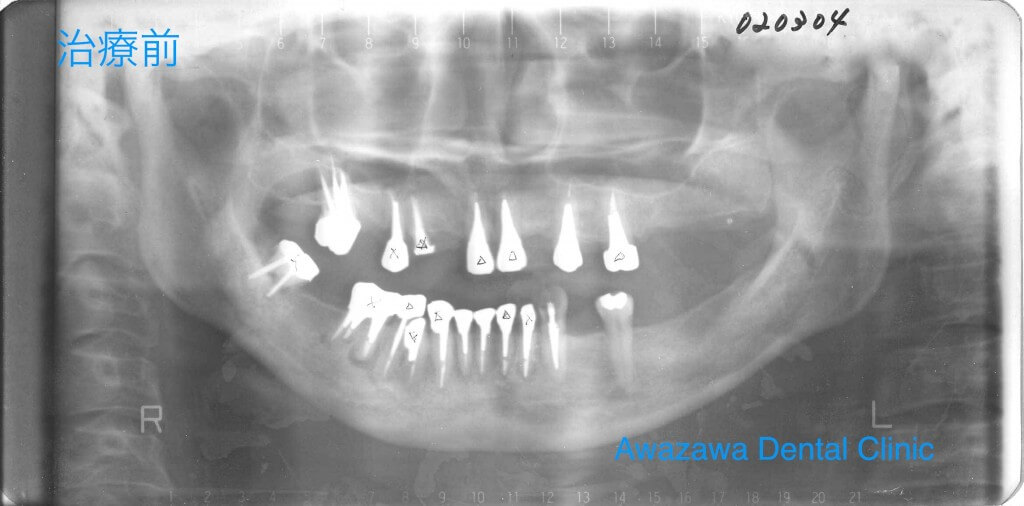

お口全体の咬み合わせを治療した症例です。治療前は左下の写真のように顎がずれて右側ではほとんど咬めない状態でした。また、顎の関節が痛く顎関節症状を呈していらっしゃいました。

セラミッククラウンとダイレクトボンディングによる最小修復と一部インプラントによる再建により治療後は咬み合わせが正常となり顎関節症状も消失し、併せて審美性も良好となり快適に過ごされていらっしゃいます。(治療後の写真は治療終了6年経過後の状態です)